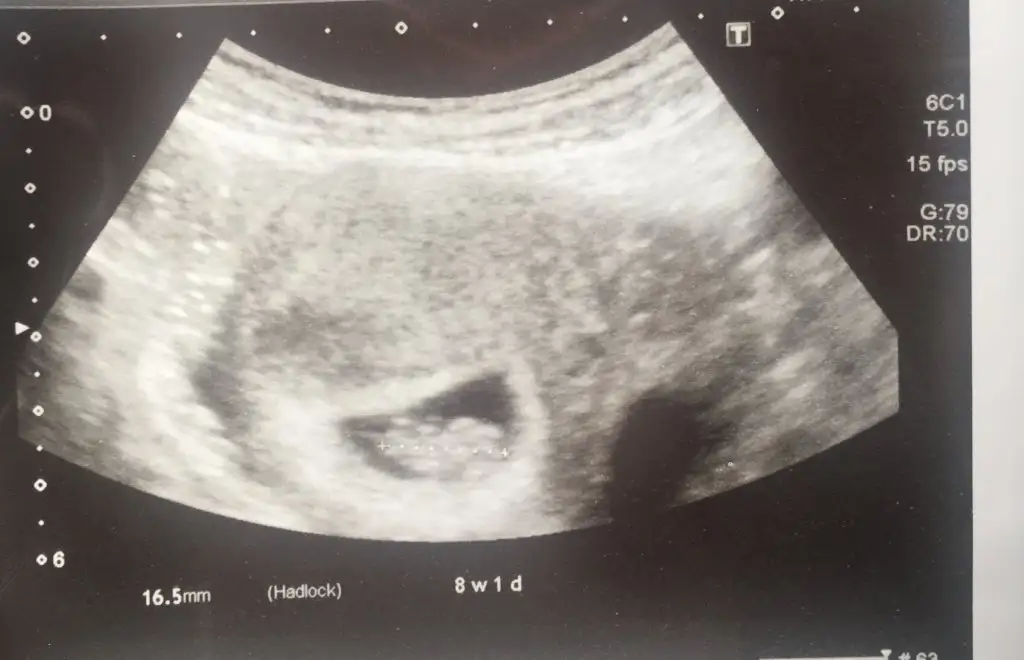

Buna göre erkek siz nub için 11 yada 12 hafta usg paylaşınMerhabalar 7+1 günlük alttan ultrason tahmin alabilirmiyim.

Teşekkür ederim cevabınız için 11 12 haftada da atarım bu dünkü ultrasonumuzdu.Buna göre erkek siz nub için 11 yada 12 hafta usg paylaşın